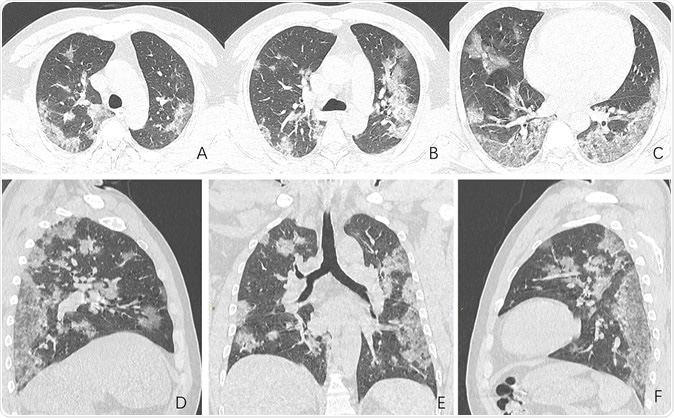

Images in a 44-year-old man who presented with fever and suspected COVID-19 pneumonia. A-C, Thin-slice (1-mm) axial CT images showed multiple patchy ground-glass opacity along the peribronchial and subpleural lungs. Some reticular opacities were also found within areas of ground glass (crazy-paving pattern). Lymphadenopathy was absent. D-F, Multiplanar reconstruction showed diffuse distribution of lesions.

The study examines the chest X-rays, and CT scans from over 20 patients aged 10-74 years, with symptoms of COVID-19. The scans showed inflamed lungs with ground-glass opacities, which look like white lung patches. These opacities are due to the partial clogging of the lung alveoli with tenacious mucus. Autopsies of Chinese patients who died of the illness because of breathing difficulties show lungs with minimal capacity for air inhalation due to the mucus accumulation.

The RSNA study shows how fluid accumulation in the lungs slowly worsens as the illness progresses, but then drains away if recovery begins until the lung spaces are completely clear.